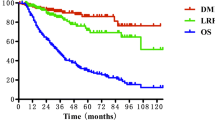

The follow-up period began on the last day of radiotherapy, and the last follow up was 31 March 2012. The median follow-up time was 78 months (range: 60–96 months). Of 208 patients, 180 (86.5%), 13 (6.25%), 5 (2.4%), 2 (0.48%) and 4 (1.92%) patients experienced one or more late toxic effects within 12 months, 13–24 months, 25–36 months, 37–48 months and 49–60 months after receiving treatments, respectively. The most common late injury was cervical subcutaneous fibrosis, with an occurrence rate of 89.9%. Hearing loss, skin dystrophy and xerostomia had occurrence rates of 67.8%, 47.6% and 40.9%, respectively. Trismus, temporal lobe injury, cranial nerve damage, cataract and brain stem injury had occurrence rates of 7.21%, 4.33%, 2.88%, 1.44% and 0.48%, respectively. No spinal cord injuries or mandible injuries were found. Xerostomia decreased gradually over time. In contrast, hearing loss, skin dystrophy, and cervical subcutaneous fibrosis increased gradually over time (Figure 1).

Xerostomia was recorded in 80.8%, 66.3%, 56%, 40.9% and 40.9% of patients within 1, 2, 3, 4 and 5 years after RT, respectively. The incidence decreased gradually over time and then stabilised within the 4 years after RT. No grade 3–4 xerostomia was found (Figure 2).

The incisor distance stabilised by 1 year after RT in all patients. Trismus was recorded in 3.37%, 3.37%, 5.29%, 5.77% and 7.21% patients within 1, 2, 3, 4 and 5 years after RT, respectively. No grade 3–4 trismus developed. The mean incisor distance of 208 patients was 4.54 ± 0.5 cm before radiotherapy and decreased to 4.3 ± 0.6 cm, 4.3 ± 0.6 cm, 4.3 ± 0.7 cm, 4.2 ± 0.7 cm and 4.2 ± 0.7 cm by years 1–5 after radiotherapy, respectively (Figure 3).

Hearing loss was also a common complication in NPC patients after conventional RT. The occurrence rate for hearing loss ranged from 54% to 82.5% in all types of clinical reports [2,3,5,16,24]. Although the occurrence rates of hearing loss in studies by Yeh [16] and by Kong [2] were similar to this study, the occurrence rates of over grade 3 hearing loss were 12.4% and 22%, respectively. Sumitsawan’s [3] study reported that the occurrence rate of over grade 3 hearing loss was as high as 36%, while only a 0.96% occurrence rate of over grade 3 hearing loss was found in this study, which indicated that the occurrence rate of hearing loss was significantly improved by IMRT. This result was similar to that reported by Xiao [13]; although the incidence rate of grade 1–2 hearing loss was 91.2%, no grade 3–4 hearing loss was observed. Our study also showed that the incidence of hearing loss increased gradually during the 5 years of follow-up after IMRT, which suggested that hearing loss presented gradually over time after RT and that once hearing loss occurred, it could not be recovered.